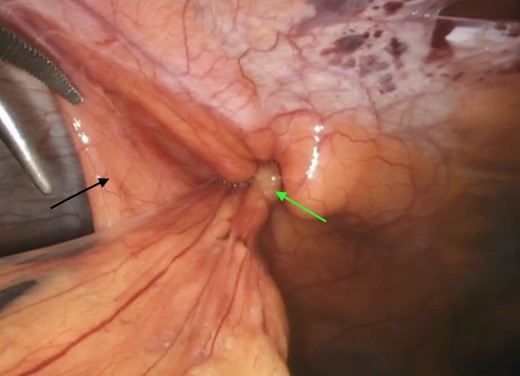

A computerized tomography (CT) scan demonstrated a chronic ventral hernia (Fig. 1) containing fat anterior to the left lobe of the liver which had marginally increased in size from a previous study done a year earlier. Through judicious use of analgesia, the hernia was successfully reduced. Two weeks later, the patient underwent a laparoscopic transabdominal pre-peritoneal (TAPP) mesh repair (Fig. 2). Laparoscopic visualization revealed, along with viable incarcerated omentum (Fig. 3), a falciform ligament hernia extending into the abdominal wall in the epigastrium.

Incarcerated omentum (green arrow) within the falciform ligament (black arrow).